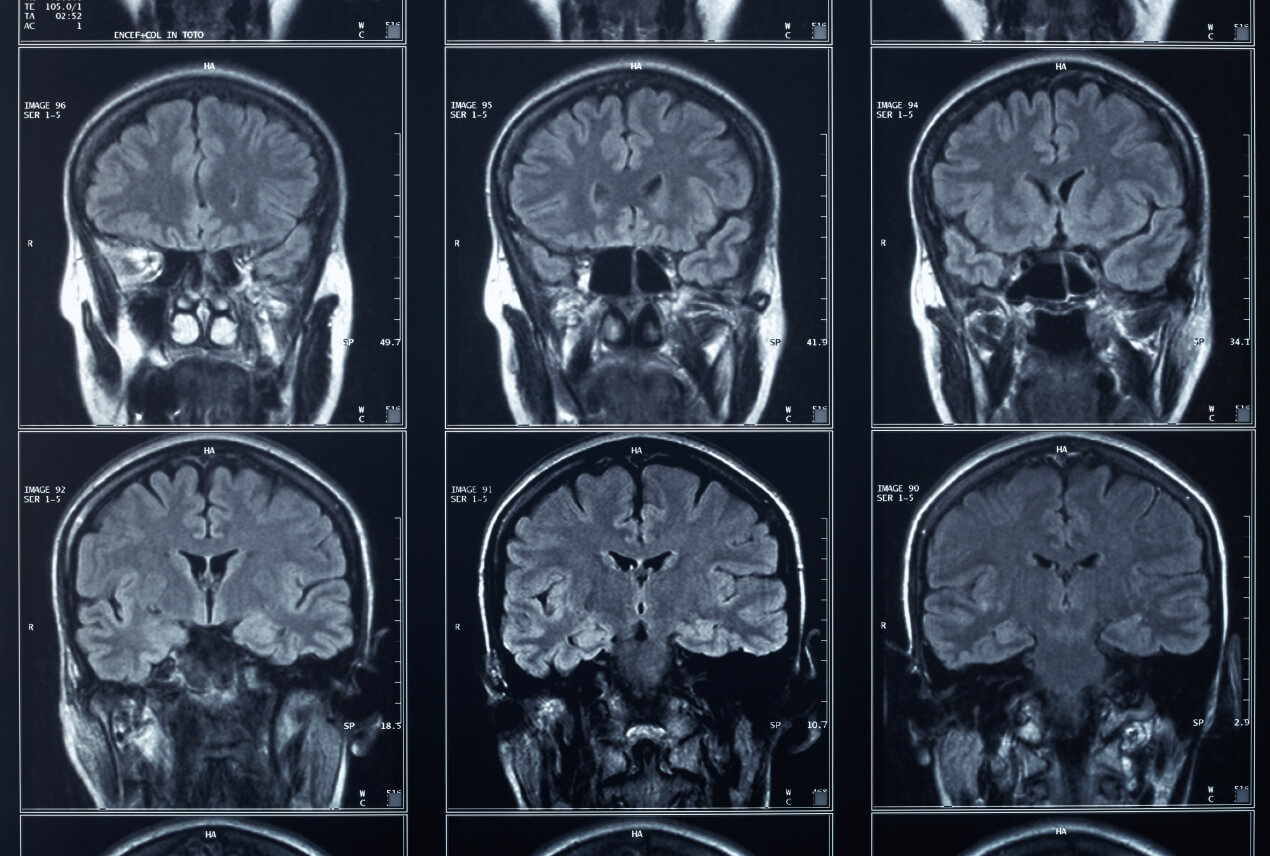

Alzheimer's disease is a neurodegenerative disease that causes progressively significant impairments in behavior and cognition, including speech production and comprehension, focus, recall and complex reasoning skills. It's the most common subtype of dementia, a generalized term that alludes to cognitive decline so severe it interferes with activities of daily living.

The disease predominantly affects seniors: onset prior to age 65 is rare. There is no cure, and diagnosis in the early stages is cumbersome because Alzheimer's has no definitive tests, but treatments exist to help manage or slow symptoms.